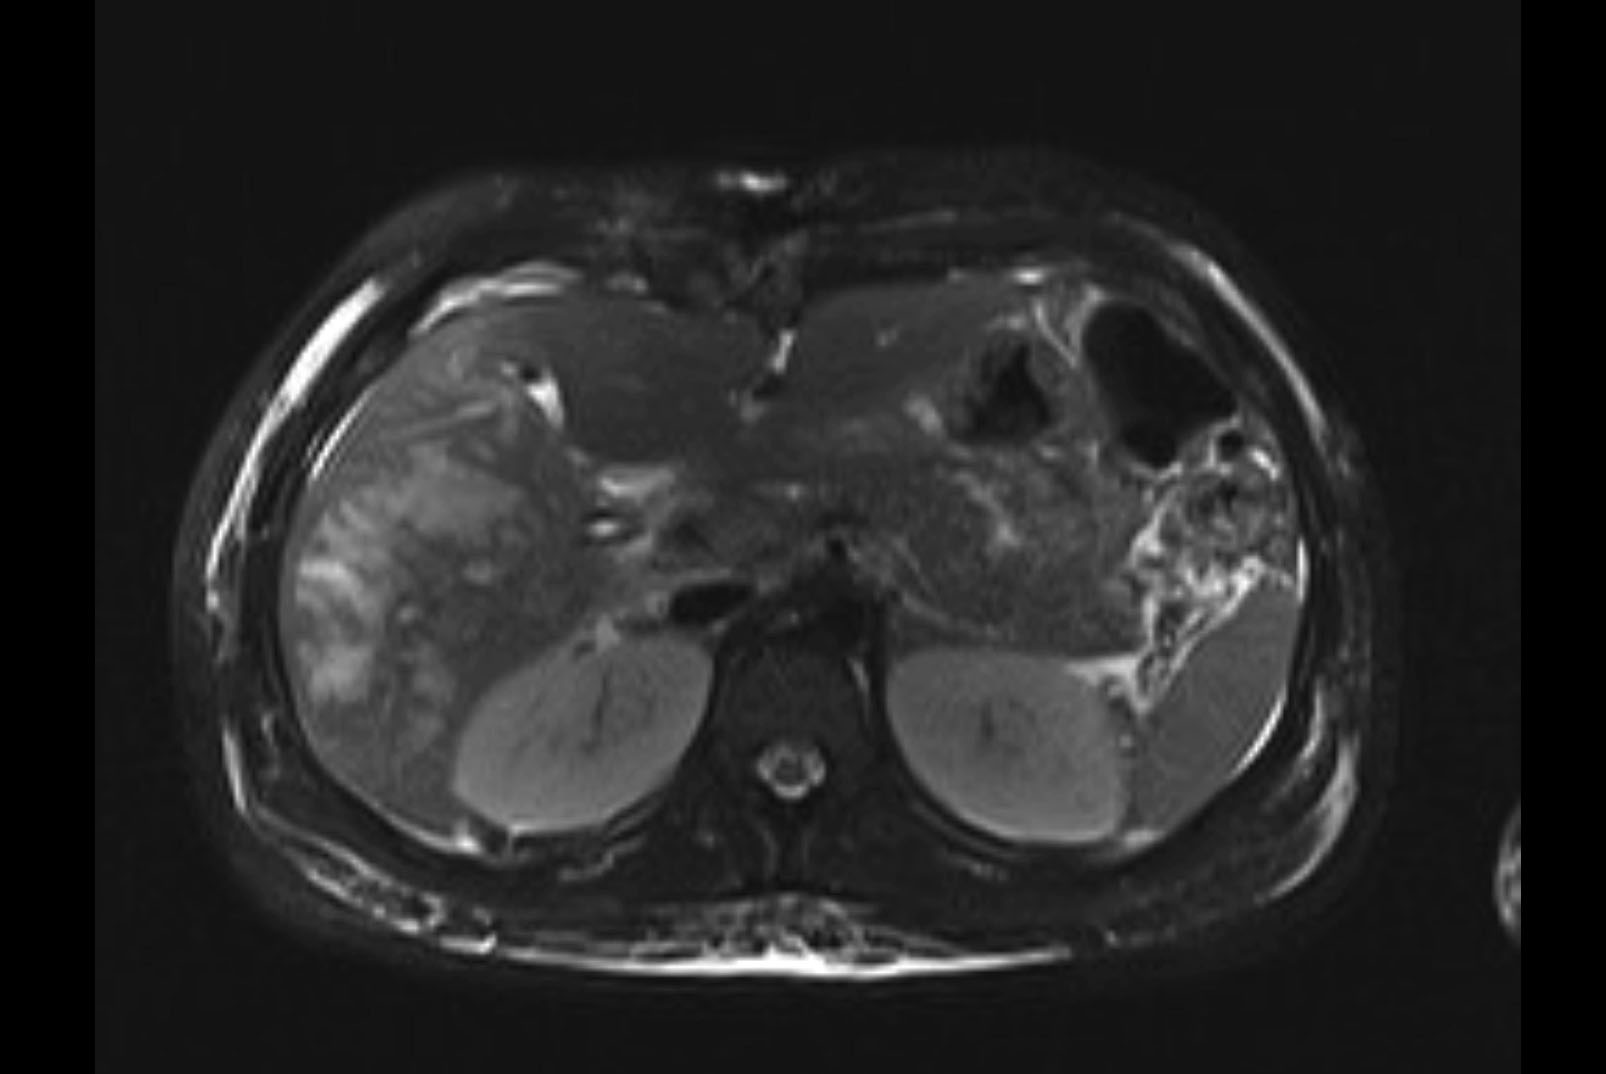

MRI T1